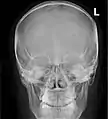

Lateral projection of the paranasal sinuses

Paranasal sinuses are a group of four paired air-filled spaces that surround the nasal cavity.[1] The maxillary sinuses are located under the eyes; the frontal sinuses are above the eyes; the ethmoidal sinuses are between the eyes and the sphenoidal sinuses are behind the eyes. The sinuses are named for the facial bones and sphenoid bone in which they are located. Their role is disputed and no function has been confirmed.